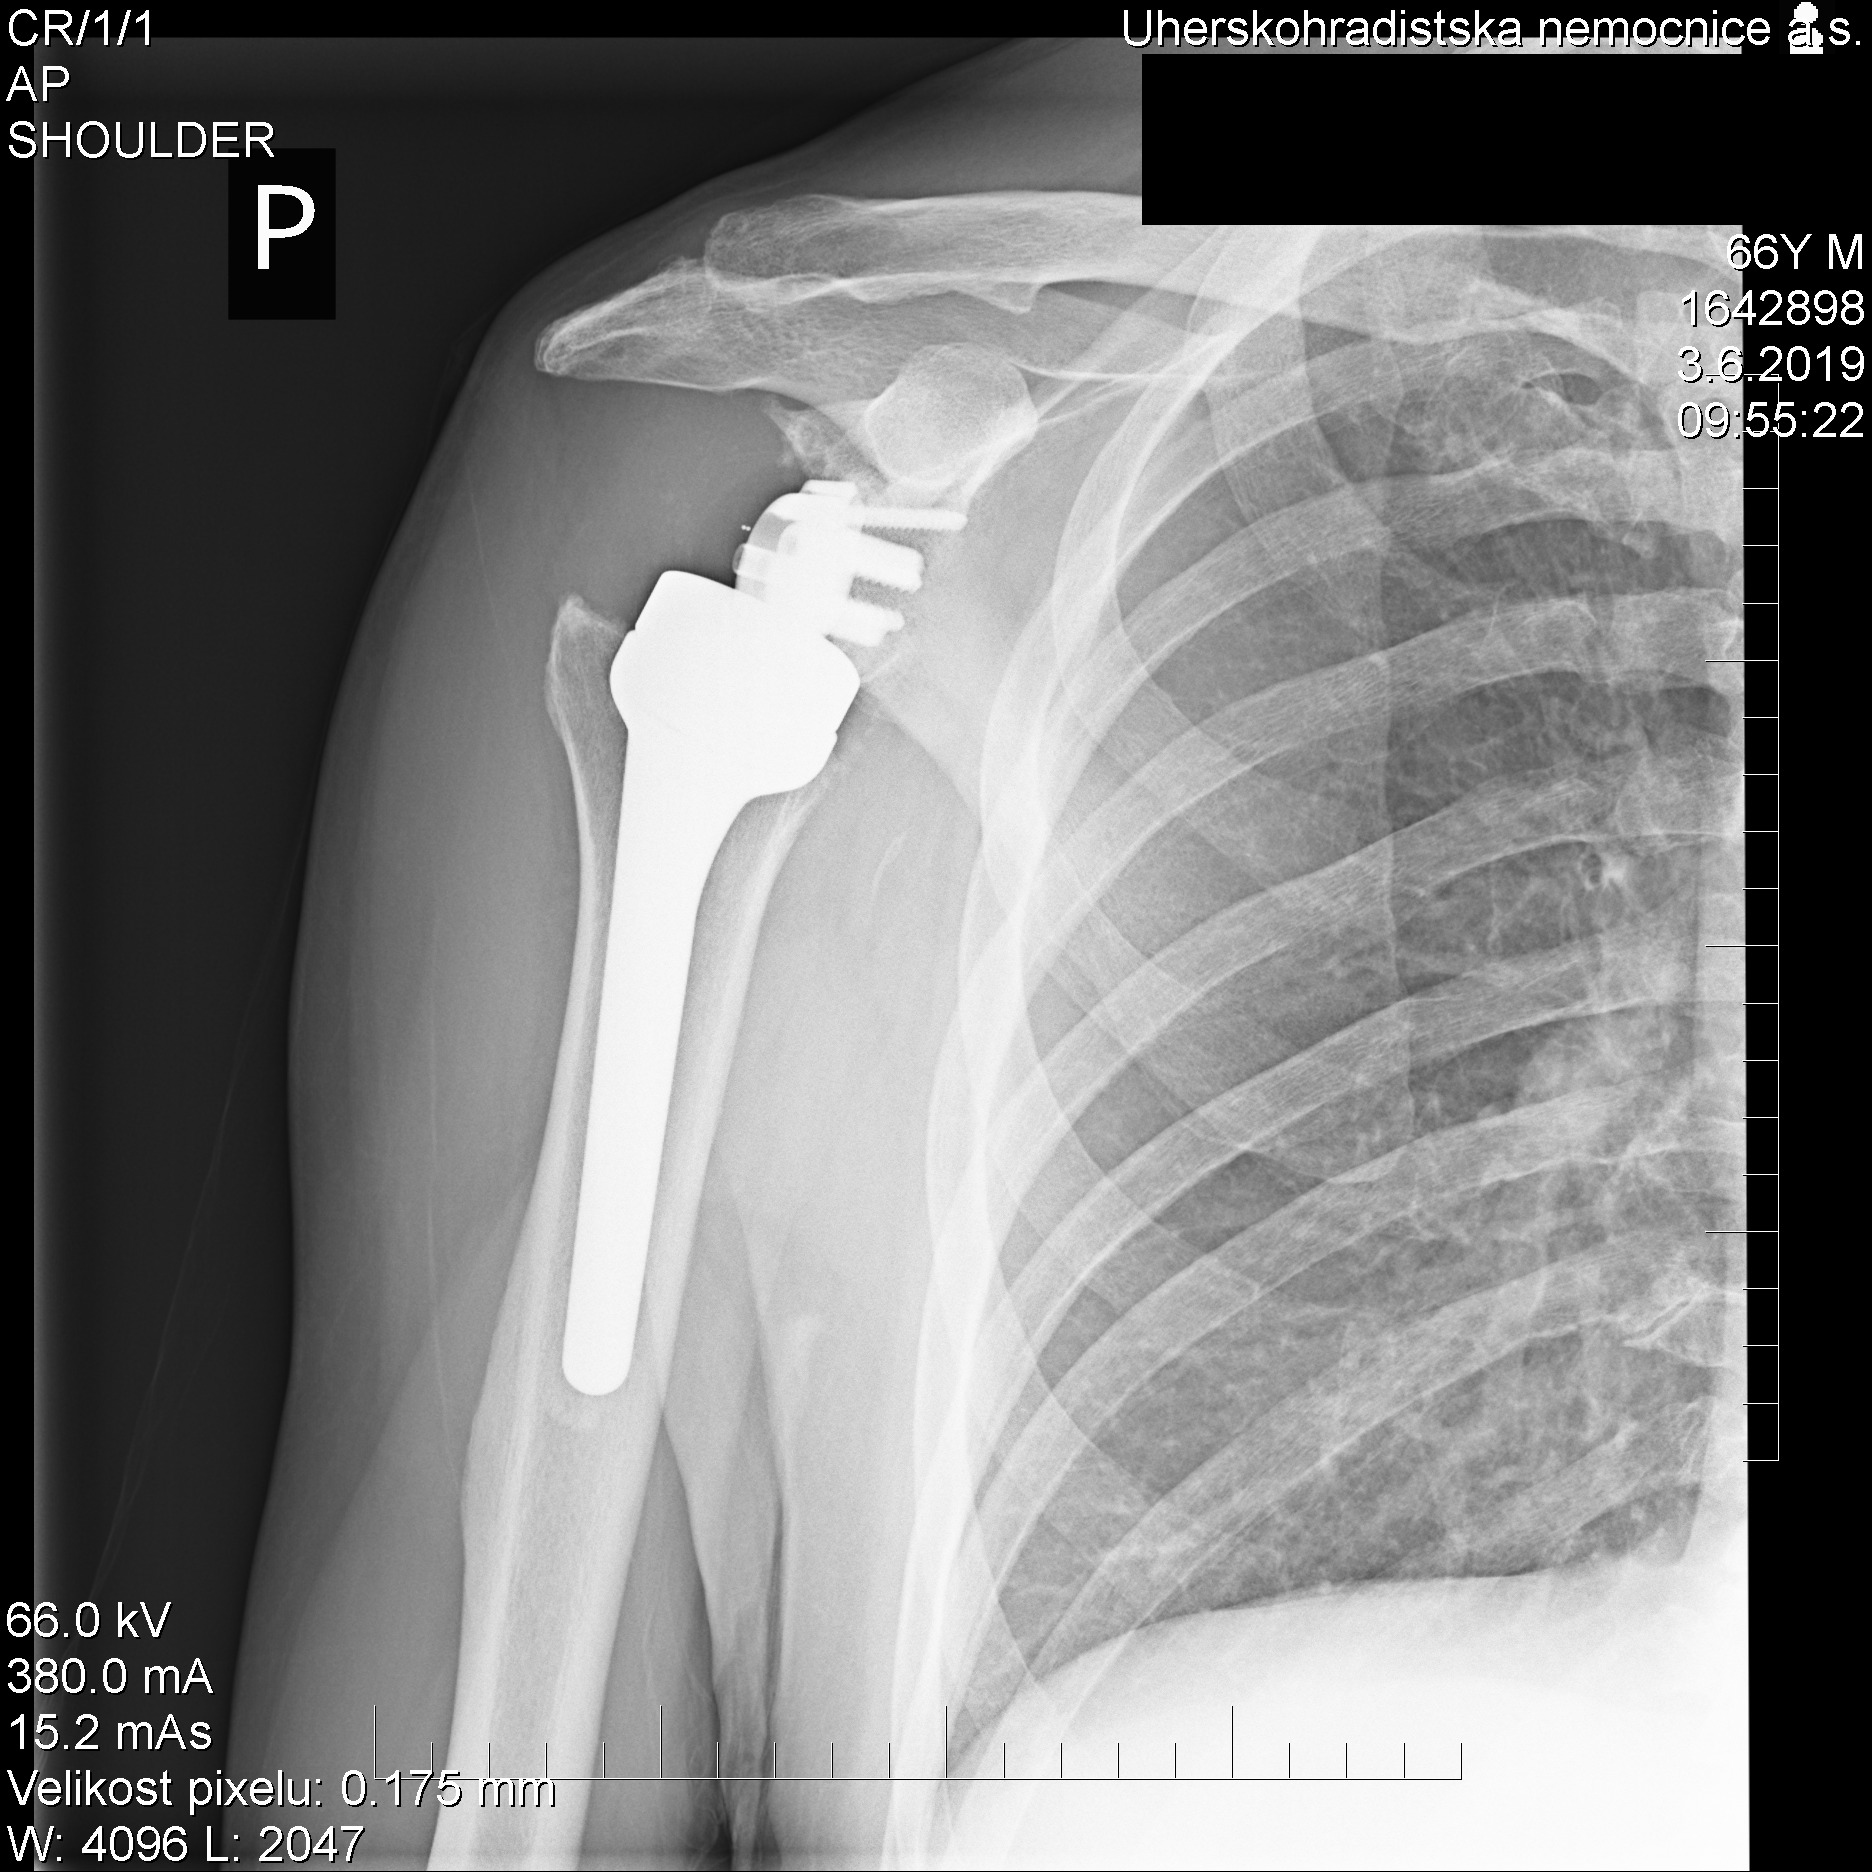

„Náhrada ramenního kloubu má svá specifika. Atypická je například v tom, že se původní hlavice pažní kosti mění v jamku, přičemž hlavice endoprotézy se kotví do lopatky. Právě tato záměna, tedy reverzní náhrada kloubu, pak umožňuje plnou hybnost a stabilitu ramene. „Kotvení náhrady právě do lopatky je navíc dost nesnadné a limitované, jedná se totiž o kost docela tenkou a subtilní,“ popisuje princip náhrady ramenního kloubu primář Ortopedického oddělení Uherskohradišťské nemocnice Martin Skládal.